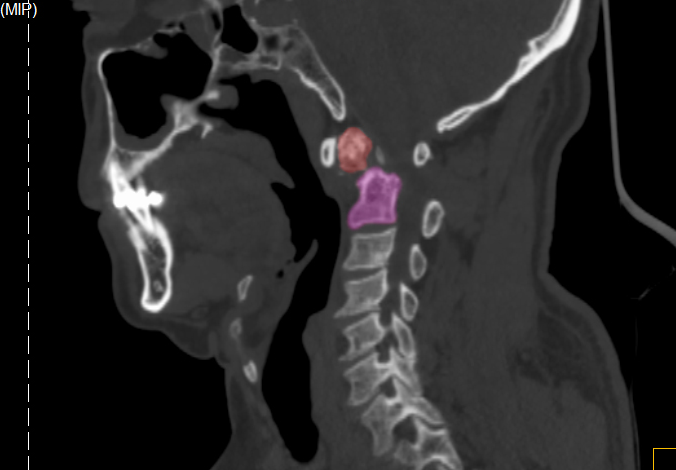

今年8月下旬,王先生因雙上肢酸痛、麻木難忍一月余才來就診。X線檢查顯示,王先生樞椎陳舊性骨折不愈合。脊柱創傷外科醫療團隊詳細評估認為,患者寰椎樞椎極度不穩定,隨時可能截癱進而危及生命,需盡快手術治療。此時,王先生毅然選擇手術,解決“折磨”了自己30余年“心頭大患”。

王先生術前CT